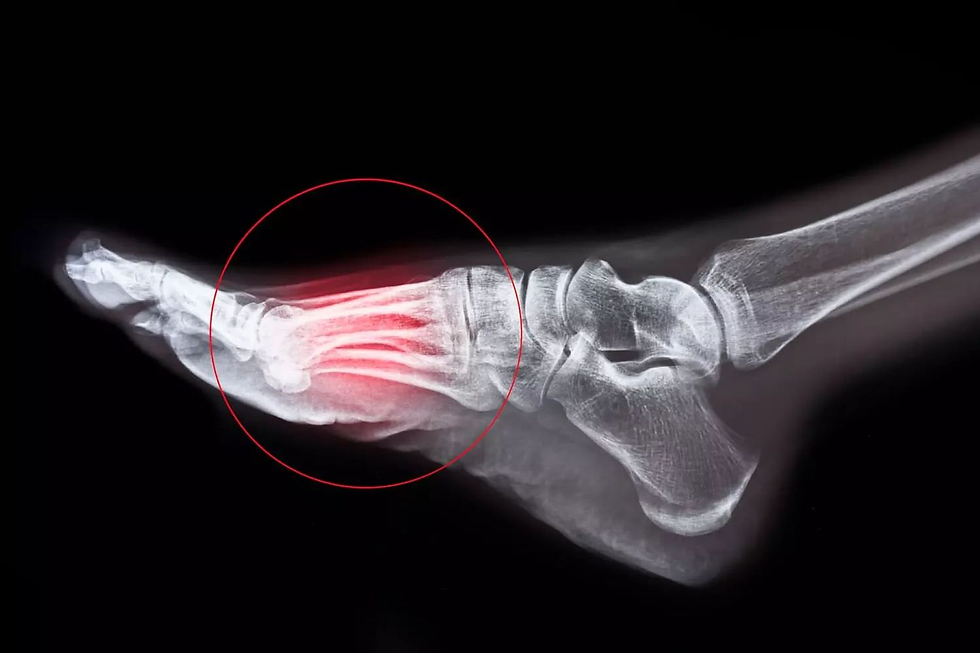

Le Doc : Votre IRM confirme le diagnostic évoqué à l’issue de nos échanges et de votre examen clinique. Vous avec une fracture de fatigue du col du deuxième métatarsien.

Le Doc : Votre os a fonctionné comme un fusible ! Il a été particulièrement sollicité sur les irrégularités de terrain et sur le relief. Les métatarsiens sont les petites baquettes osseuses qui relient les orteils à la cheville. Ils agissent comme un clavier pour épouser les aspérités du sol. Le deuxième, celui que vous avez cassé, est souvent le plus long. Quand vous montez, pour épouser la pente, vous mettez vos doigts de pieds en extension, vous tordez un peu la partie étroite de votre second métatarsien. A la manière d’un petit fil de fer contorsionné, il a fini par casser. Revêtement accidenté et beaucoup de dénivelé, deux paramètres auxquels vous n’étiez pas adaptés ! Tout est cohérent !